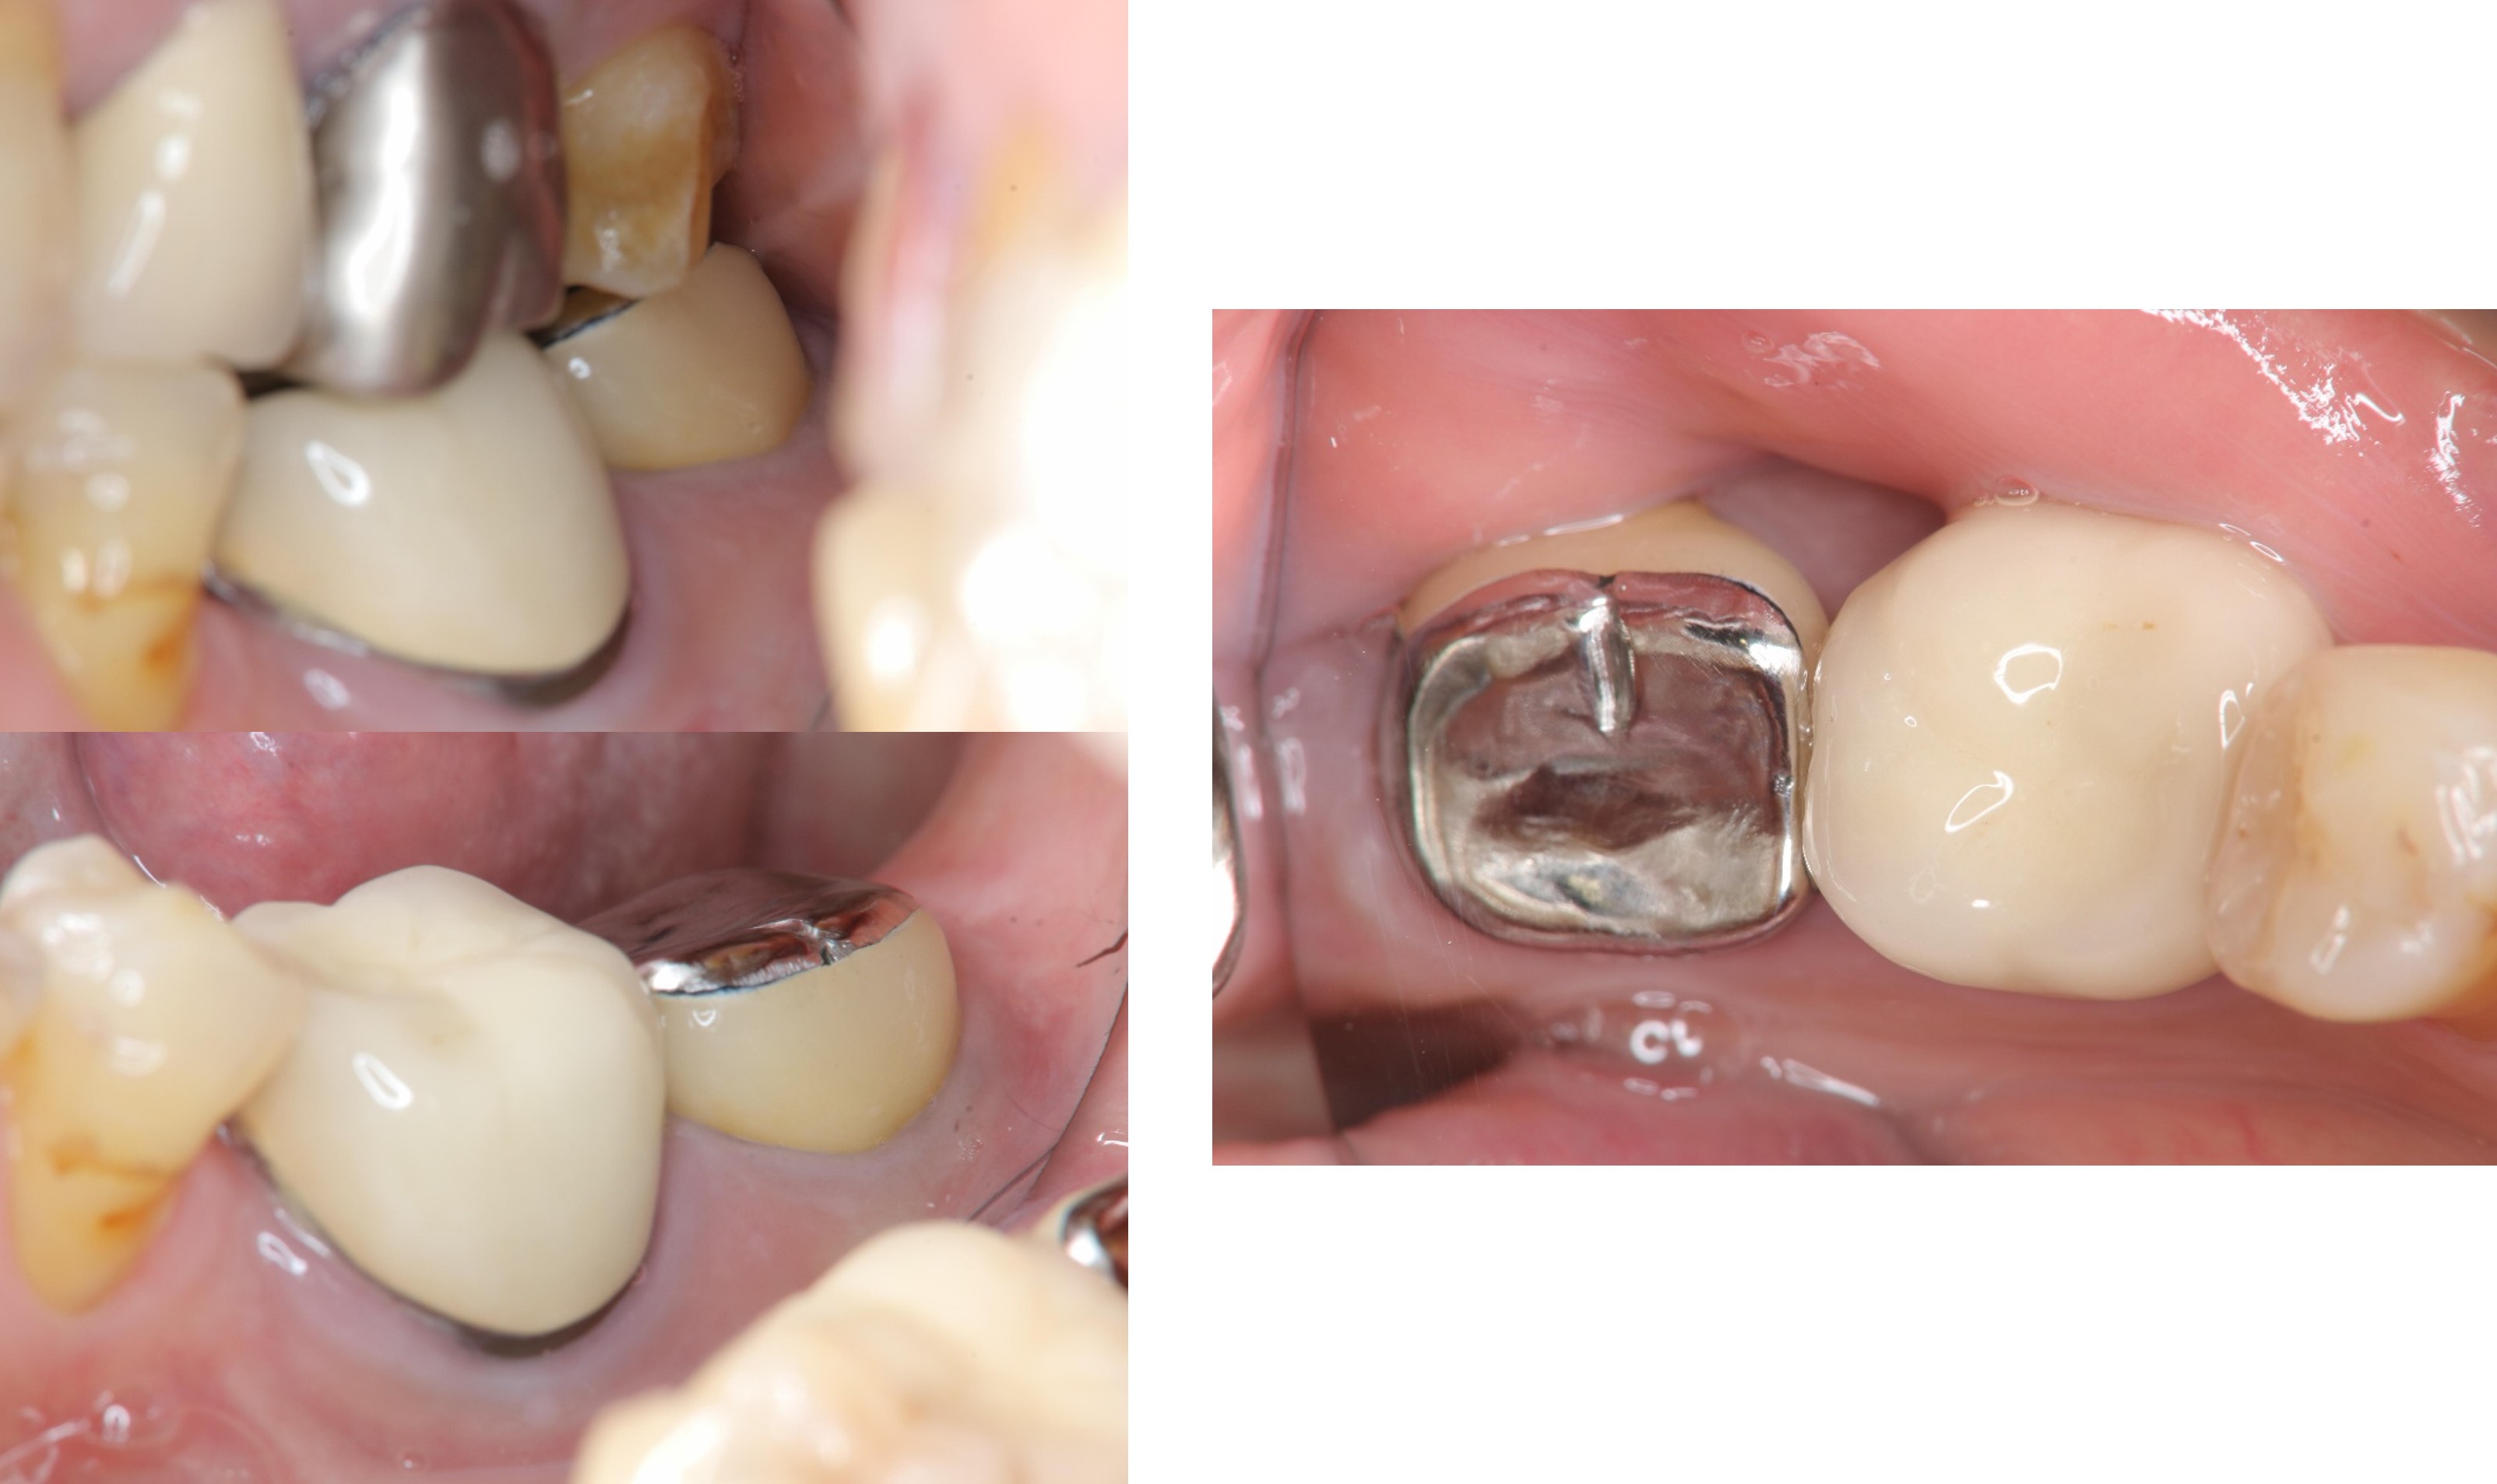

治療前,左下第二大臼齒假牙常脫落,前來求診

牙冠增長手術

牙齒印模前追蹤

治療後口內照